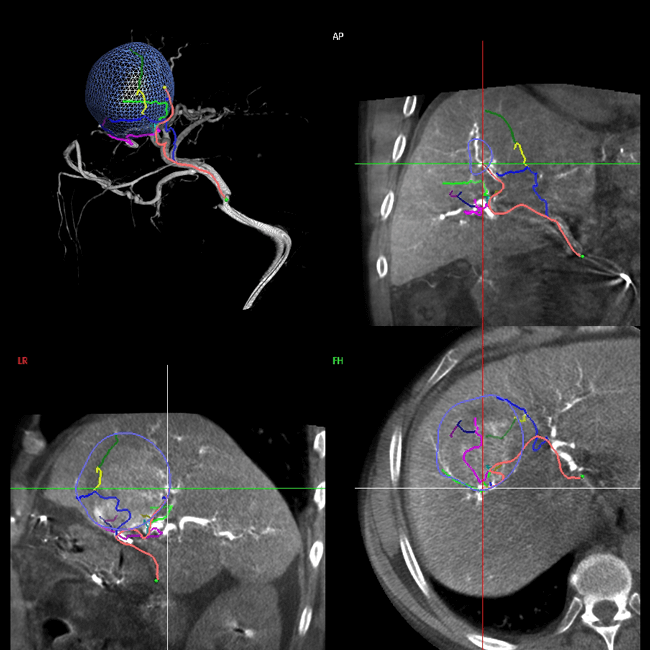

• Sistema Emboguide: identifica las ramas tumorales para la embolización de tumores, con ahorro de medio de contraste u dosis de radiación.

• Fusión de imagen 2D y 3D, funciona para realizar intervenciones en la aorta abdominal.

• Adquisición de bajo contraste para hígado, abdomen y de arteria prostática.

• Adquisición tridimensional.

• Software para evaluación del patrón de flujo dentro del aneurisma.